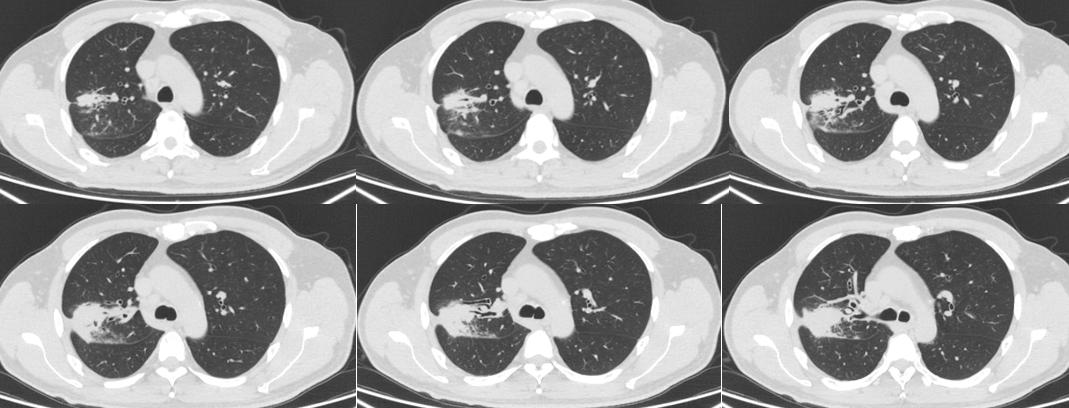

病例一

病史:男性,50岁,主诉:咳嗽咳痰6月,发热半月

影像描述:右肺可见多发班片状、条片状、索条状密度增高灶,边界不清,边缘呈磨玻璃密度,病变内可见多发低密度区,增强扫描可见明显强化,低密度区未见明显强化,边界清,局部可见小空洞形成,周围可见多发纤维条索灶,与胸膜牵连,邻近胸膜及叶间裂局部增厚,病变区支气管管壁明显增厚。左肺下叶前内基底段胸膜下见一实性结节,截面大小约 0.6cm。段及段以上支气管通畅。右肺门及纵隔可见多发肿大淋巴结,大者大小约 2.2x1.2c。双侧胸腔未见明显液性密度灶。扫描野示肝左叶可见一类圆形异常强化灶,大小约 1.0cm;双侧肾上腺增粗。

影像诊断:右肺多发病变并右肺门、纵隔多发淋巴结肿大,首先考虑机化性肺炎,建议病理学检查除外瘤;

病理:未查见癌细胞,考虑机化性肺炎。